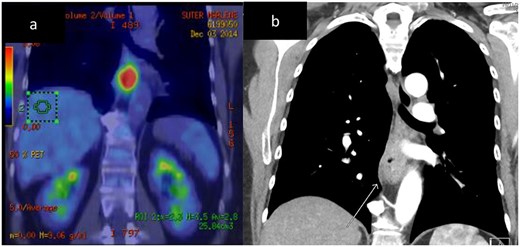

Histopathology demonstrated an SC NEC with pathological stage T2N0. Lymphovascular space invasion was present (Fig. 3). Nine lymph nodes were negative for metastases.

Case 2. Histopathology of the primary tumour. (a) and (b) demonstrates intact overlying oesophageal squamous mucosa, undermined by the infiltrative small cell lesion with invasion of the lamina propria (c), muscularis propria (d), vessels (e) and nerves (f).